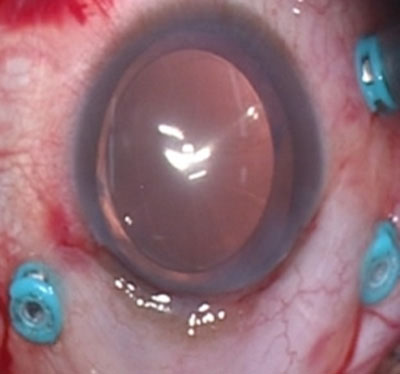

上左図 増殖性糖尿病網膜症で網膜に牽引がある状態

上右図 術後 牽引がとれて視力も回復した

上左図 糖尿病黄斑症の術前RV=(0.3)

上右図術後1RV=(0.9)視力回復し、歪みがましになった